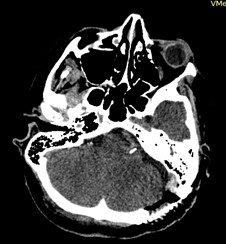

По данным МРТ головного мозга визуализировано нетипичное предлежание сразу трех внутричерепных сосудов к корешку левого лицевого нерва в зоне его выхода из вещества моста: колена базилярной, петли ветви  верхней мозжечковой и передней нижней мозжечковой артерий (рис. 1). Значительно чаще при гемифациальном спазме отмечается компрессия корешка лицевого нерва только одним сосудом. По данным электронейромиографии при стимуляции височной ветви левого лицевого нерва получен прямой М-ответ от лобной мышцы (переднее брюшко лобно-затылочной мышцы) и патологический ответ от подбородочной мышцы с увеличенной латентностью и амплитудой до 15% от амплитуды прямого М-ответа.

Рис. 1. МРТ головного мозга в аксиальной и коронарной проекциях: отмечается близкое расположение петли базилярной, петли ветви верхней мозжечковой и передней нижней мозжечковой артерий к корешку левого лицевого нерва в зоне его выхода из вещества моста.